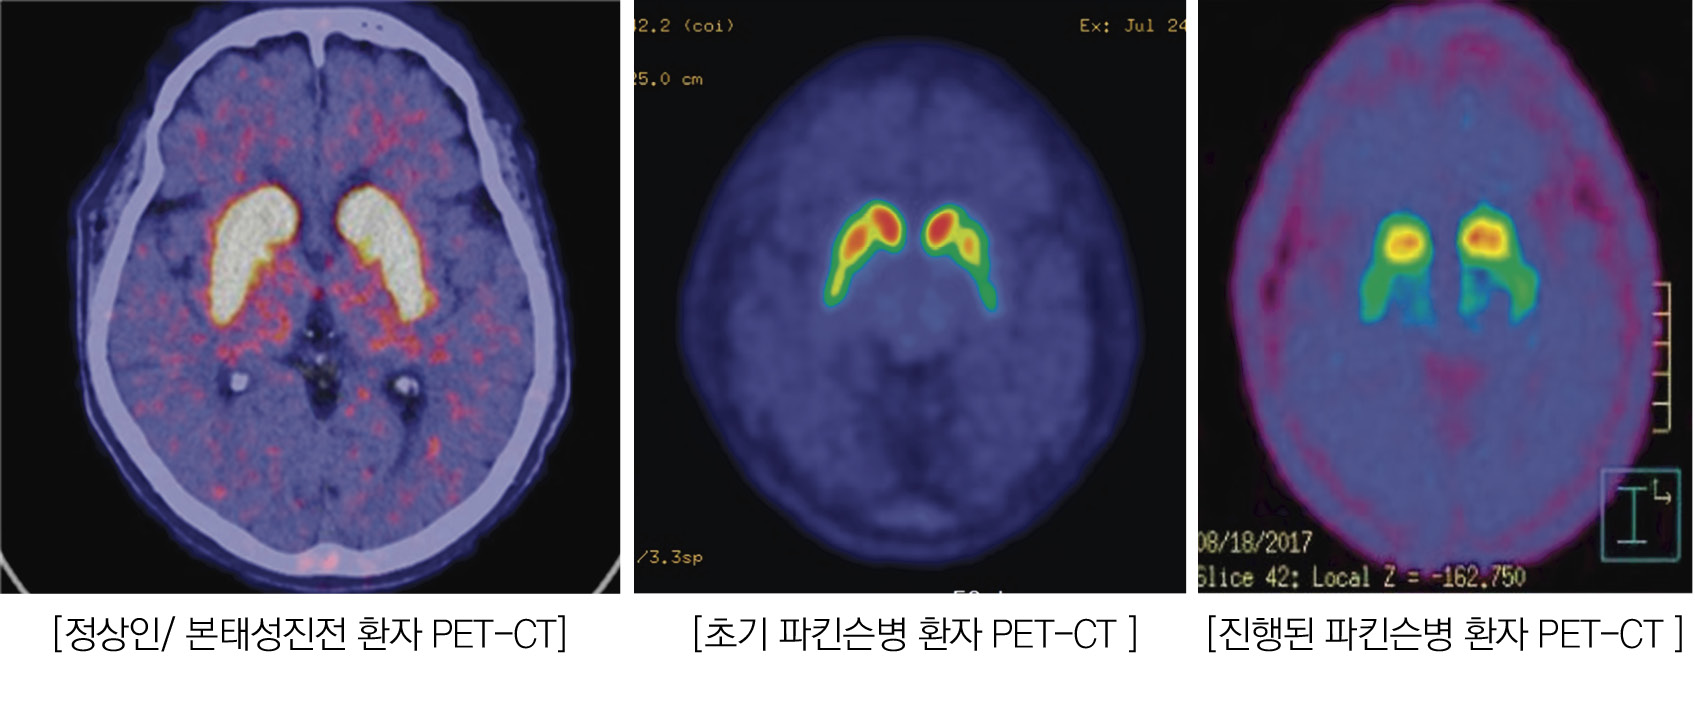

또 하나의 요소는 영상진단의 보편화도 한 몫을 하고 있다. 파킨슨병의 대표적 표준진단지표 중 하나인 PET-CT의 보편화로 진단의 정확도가 개선되고 조기진단이 가능하게 되어 잠재적 질병 시기가 짧아진 것이다.